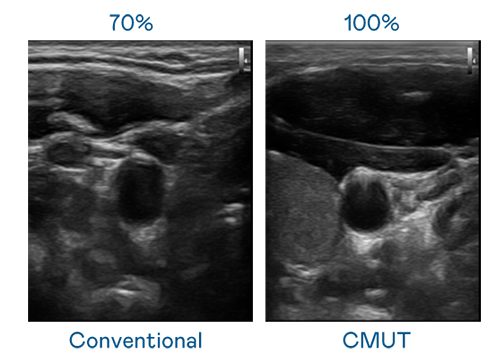

CMUT 技术是一种用电容式微机电元件来产生超音波讯号的技术。与传统 PZT 压电式技术相比,CMUT 频宽增加 30%,更宽频的超音波讯号让影像解析度大幅提升,是实现高影像品质医疗超音波扫描、促进精准医疗发展的关键技术。

大频宽带来超清晰影像

超音波影像的解析度高低,首先取决于探头能发出的讯号频宽。龙门国际 CMUT 可提供高清晰的超音波讯号,提供高频宽、高灵敏度、影像纹理细节更高的超音波影像,协助医护人员缩短影像判读时间及利用精准的医疗影像进行诊断。